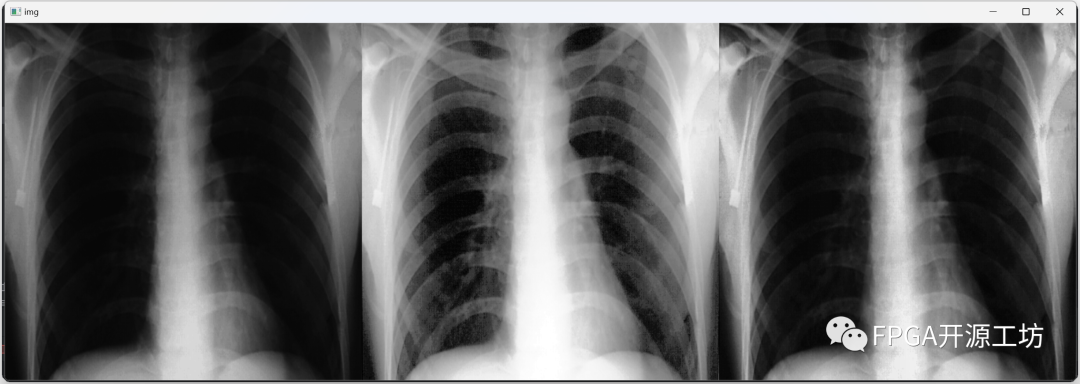

最左侧为原图,中间为直方图均衡化后的结果,最右侧为CLAHE算法的效果。

从视觉效果上来看,CLAHE算法的效果最为明显。